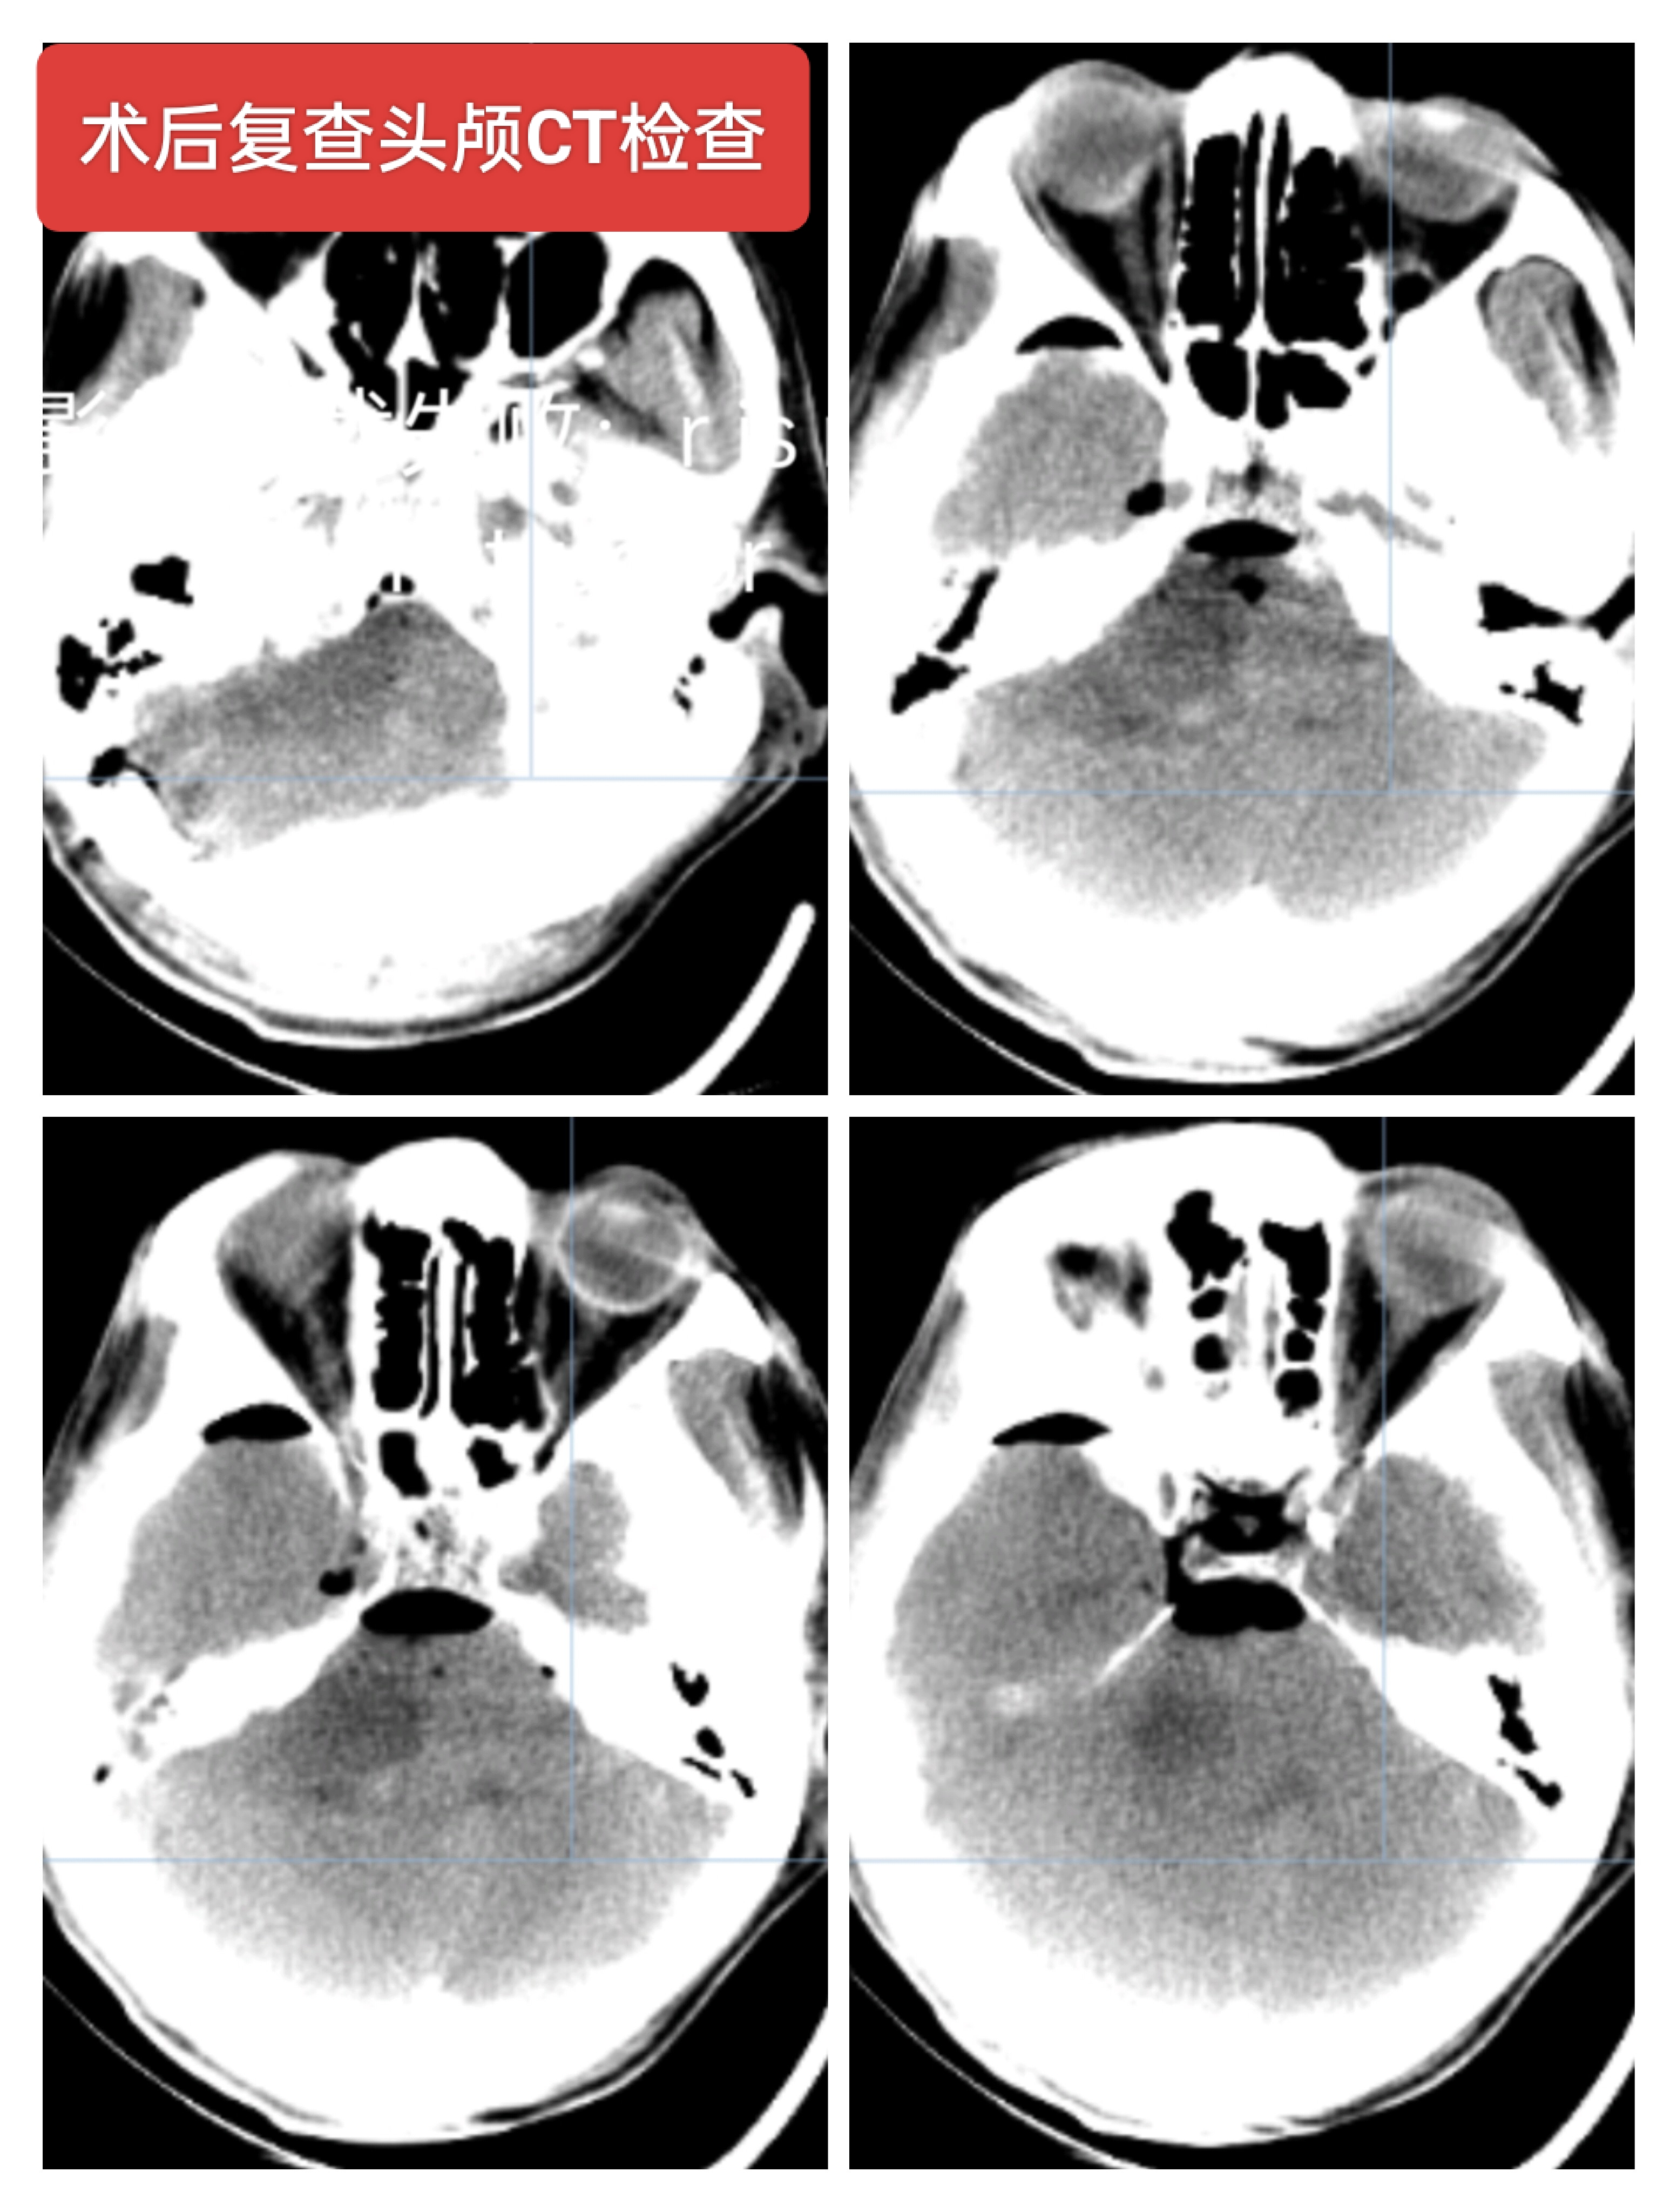

右侧听神经瘤,男性64岁,听力下降一年主诉入院,核磁检查提示右侧CPA区囊实性占位,大小约5cm左右,常规行神经电生理监测下肿瘤切除术,术中面神经保留,术后轻度面瘫。